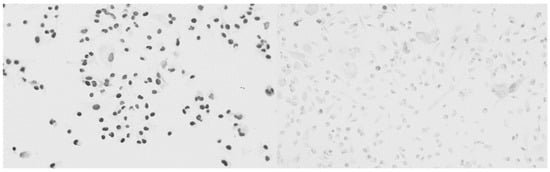

2.1. Cell Proliferation

2.2. Analysis of the Cytotoxic Effects